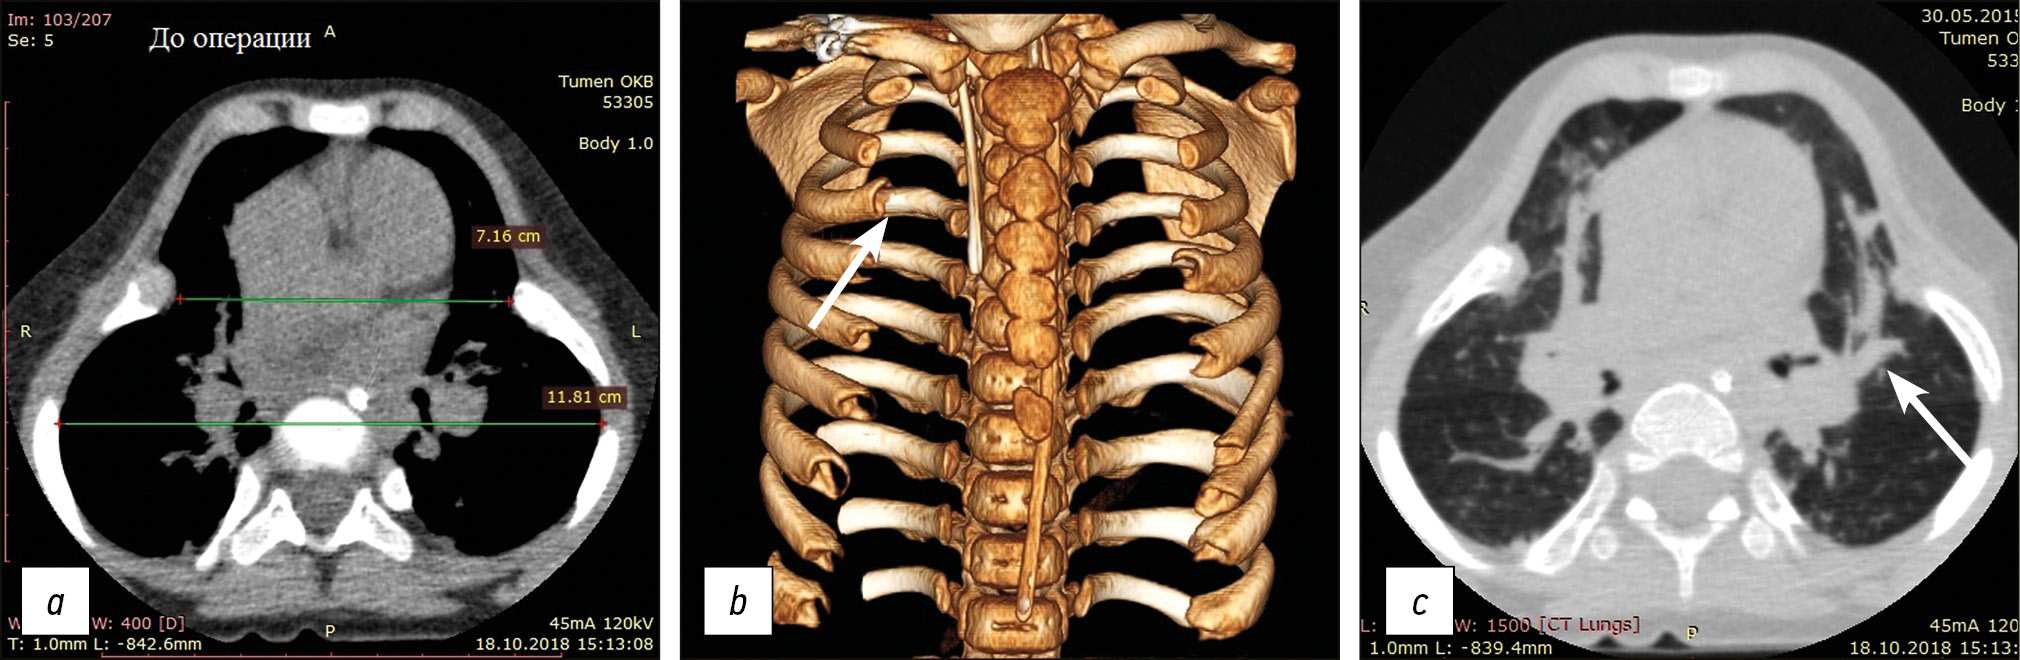

При мультиспиральной компьютерной томографии (МСКТ) грудной клетки выявлены изменения, характерные для синдрома Жёна: грудная клетка симметрично «сдавлена» в поперечном направлении. Ребра имеют горизонтальную ориентацию, их передние костные отделы «бокаловидно» расширены (рис. 1). Компрессия обоих легких «вдавленными» отделами ребер сопровождается нарушением пневматизации, диффузным неравномерным нарушением структуры легочной ткани, участками уплотнений, вздутий. Прослеживаются сегментарные и субсегментарные ателектазы S2, S8 правого и S4,5, S8 левого легких, а также просветы сближенных и деформированных бронхов, формирование фиброзных изменений.

Рис. 1. Компьютерная томограмма (а, с) и 3D- реконструкция (b) грудной клетки пациентки М., 3 г. 4 мес., с синдромом Жёна (тип А2S0F1cor, br) до лечения: а — аксиальный срез на вершине деформации (индекс горизонтальной компрессии грудной клетки = 60,1 %); b — узкая сегментированная грудина и короткие, широкие и плоские ребра с аномалией строения зон роста, «бокаловидным» расширением передних отделов (показано стрелкой); c — фиброателектазы в легких (показано стрелкой) в зоне сдавления каркасом грудной клетки бронхолегочного комплекса

Fig. 1. CT scan of patient M. with Jeune syndrome (type А2S0F1cor, br). Axial section at the top of the deformity: a — before treatment (HCCI = 60.1%); b — sternum is narrow, segmented, and short; ribs are wide and flat with an abnormal structure of the growth zones, and “wine glass” extensions of the anterior areas (shown by the arrow); c — fibrotic atelectases in the lungs (shown by the arrow) in the area of compression by the chest framework of the broncho-pulmonary complex (See the text for the details)

Проводившаяся терапия (антибактериальная, глюкокортикостероиды, инфузионная, гепатопротекторы, диуретики) позволила к 39-м суткам купировать пневмонию и бронхит. Однако неоднократные попытки перевести ребенка на самостоятельное дыхание оказались безуспешны, в связи с чем на этом этапе ребенок по согласованию с главным внештатным специалистом-экспертом по торакальной хирургии МЗ РФ профессором П.К. Яблонским консультирован специалистом по торакальной ортопедии. При пересмотре данных КТ констатировано, что согласно классификации врожденных пороков грудной клетки [7], данная аномалия может быть классифицирована как тип А2S0F1cor, br (симметричная деформация преимущественно в горизонтальной плоскости с функциональными нарушениями сердечно-сосудистой и дыхательной систем). Индекс горизонтальной компрессии грудной клетки (ИГКГК) (отношение поперечного размера на уровне максимальной компрессии к наибольшему поперечному размеру) [7] составляет 60,1 %.